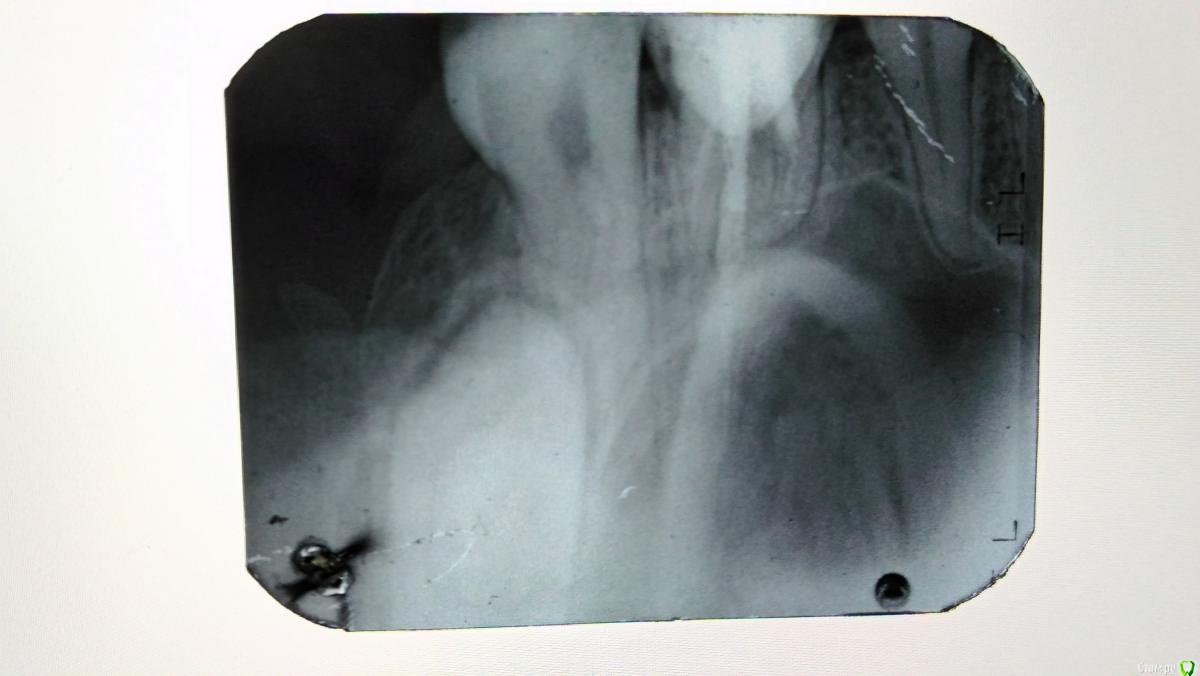

Katerina99 Опубликовано 27 июля, 2017 Поделиться Опубликовано 27 июля, 2017 Добрый день, меня беспокоит верхняя левая шестерка. Сам зуб был пару лет назад депульпирован. Запломбированный зуб иногда меня беспокоил(была боль при смыкании челюстей). Спустя некоторое время стенка зуба треснула и часть этой стенки отпала. Как оказалось позже, под пломбой был кариес. Врач убрал кариозные места и установил штифт. Через пару дней после установки я начала ощущать неприятный привкус во рту, как будто что-то просачивается. Большого внимания этому не уделила. По прошествии месяца с установки штифта я поняла, что этот неприятный привкус идет из-под десны, потому что при промывании десен ирригатором как раз и появлялся этот привкус. В пятницу ходила к врачу. Он постучал чем-то по зубу, но чувствительности абсолютно никакой не было. Да, болеть-то нечему. Боль в районе десны ощущается только при чистке зубов. Сходила сегодня на рентген. Качество снимка так себе, но, может быть, можно что-нибудь понять. И еще вопрос: где моя восьмерка непрорезавшаяся на снимке? Ссылка на комментарий

red_butler Опубликовано 27 июля, 2017 Поделиться Опубликовано 27 июля, 2017 Да, к сожалению качество снимка низкое. Требуется очный осмотр для оценки степени разрушения зуба. Если объем оставшихся твердых тканей позволяет выполнить протезирование, то повторное лечение корневых каналов у эндодонтиста и протезирование зуба искусственной коронкой. Если нет, то удаление зуба. Ссылка на комментарий